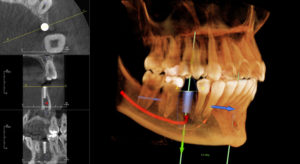

A clear path for a general practice to get to the next level is to offer a more comprehensive range of services that could potentially include endodontics, implant dentistry, and orthodontics, to name a few. With the expansion of clinical services come new challenges like the need to equip the office with more sophisticated diagnostic tools. A technology that helps address such challenges is Cone Beam 3D imaging. In particular, modern systems that provide a combination of panoramic and 3D capabilities can meet a practice’s fundamental imaging needs, as well as adding highly detailed 3D views for more complex clinical cases.

The Instrumentarium OP300 system allows ConfiDENTAL to improve the quality of services they provided to patients, Dr. Costello explains. “We have always done endodontics in our practice, and over the last five years I have incorporated implants. In the past, I had to refer my patients out for 3D scans. Now, having 3D capability in my office, I see an increase in patient acceptance of treatment plans, and 3D makes me feel much more confident in my final product.”

The OP300 Maxio provides 3D views that range from targeted, high-resolution 5cm x 5cm 3D scans, ideal for endodontic cases, up to condyle-to-condyle scans capturing the dentition, TMJs, and airway, in one single 3D scan. With clinical trends calling for a more holistic approach in dentistry, having a scalable 3D imaging system that includes multiple fields-of-view, which can aid in diagnosis and treatment planning, is essential. It’s also a smart way to anticipate the future needs of a growing general practice.